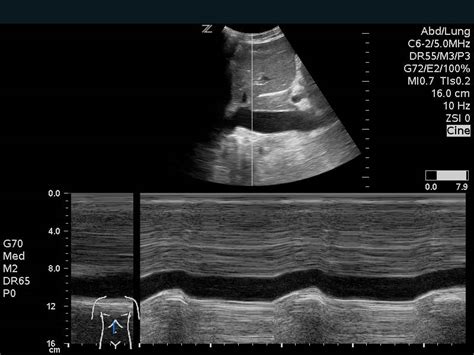

First up, we have Echocardiography . Think of this as an ultrasound of the heart. It uses sound waves to create moving pictures of your heart. It’s non-invasive, meaning there are no needles or anything like that, and it’s super useful for looking at the structure of your heart, how well it’s pumping, and how your valves are working. There are different types of echocardiograms, including transthoracic (where the probe is placed on your chest) and transesophageal (where the probe goes down your throat – a bit more involved, but it gives a clearer picture). Another common type is Electrocardiography (ECG or EKG) is often performed during stress tests to monitor the heart’s electrical activity. This test involves placing electrodes on the patient’s skin to record the heart’s electrical impulses and can provide crucial information on a variety of cardiovascular conditions.